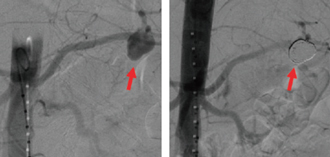

脾動脈瘤に対するコイル塞栓術

動脈瘤にカテーテルでコイル(らせん状の金属)を詰め、血流をなくす。